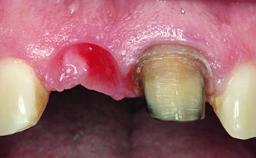

Replacement of a Failing Upper Left Central Incisor: Immediate Placement of an RC Bone Level Implant and Provisionalization

A healthy 23-year-old female patient was referred for a consultation on replacing tooth 21 with an implant-supported restoration. The patient had recently moved to the area and reported a history of endodontic and periodontal treatment for tooth 21. The tooth had been deemed non-restorable by her previous periodontist but since she was going to be moving, he recommended consulting to a dentist in her new city to continue her treatment. A review of her medical history yielded no significant findings and no known drug allergies. The analysis of her smile revealed a medium to high symmetrical smile line and a slightly discolored tooth 21.

Placement Protocol Immediate implant placement

Tooth Site Maxillary incisor or canine

Socket Morphology Single-root socket

Socket Integrity Damage to one or more bone walls